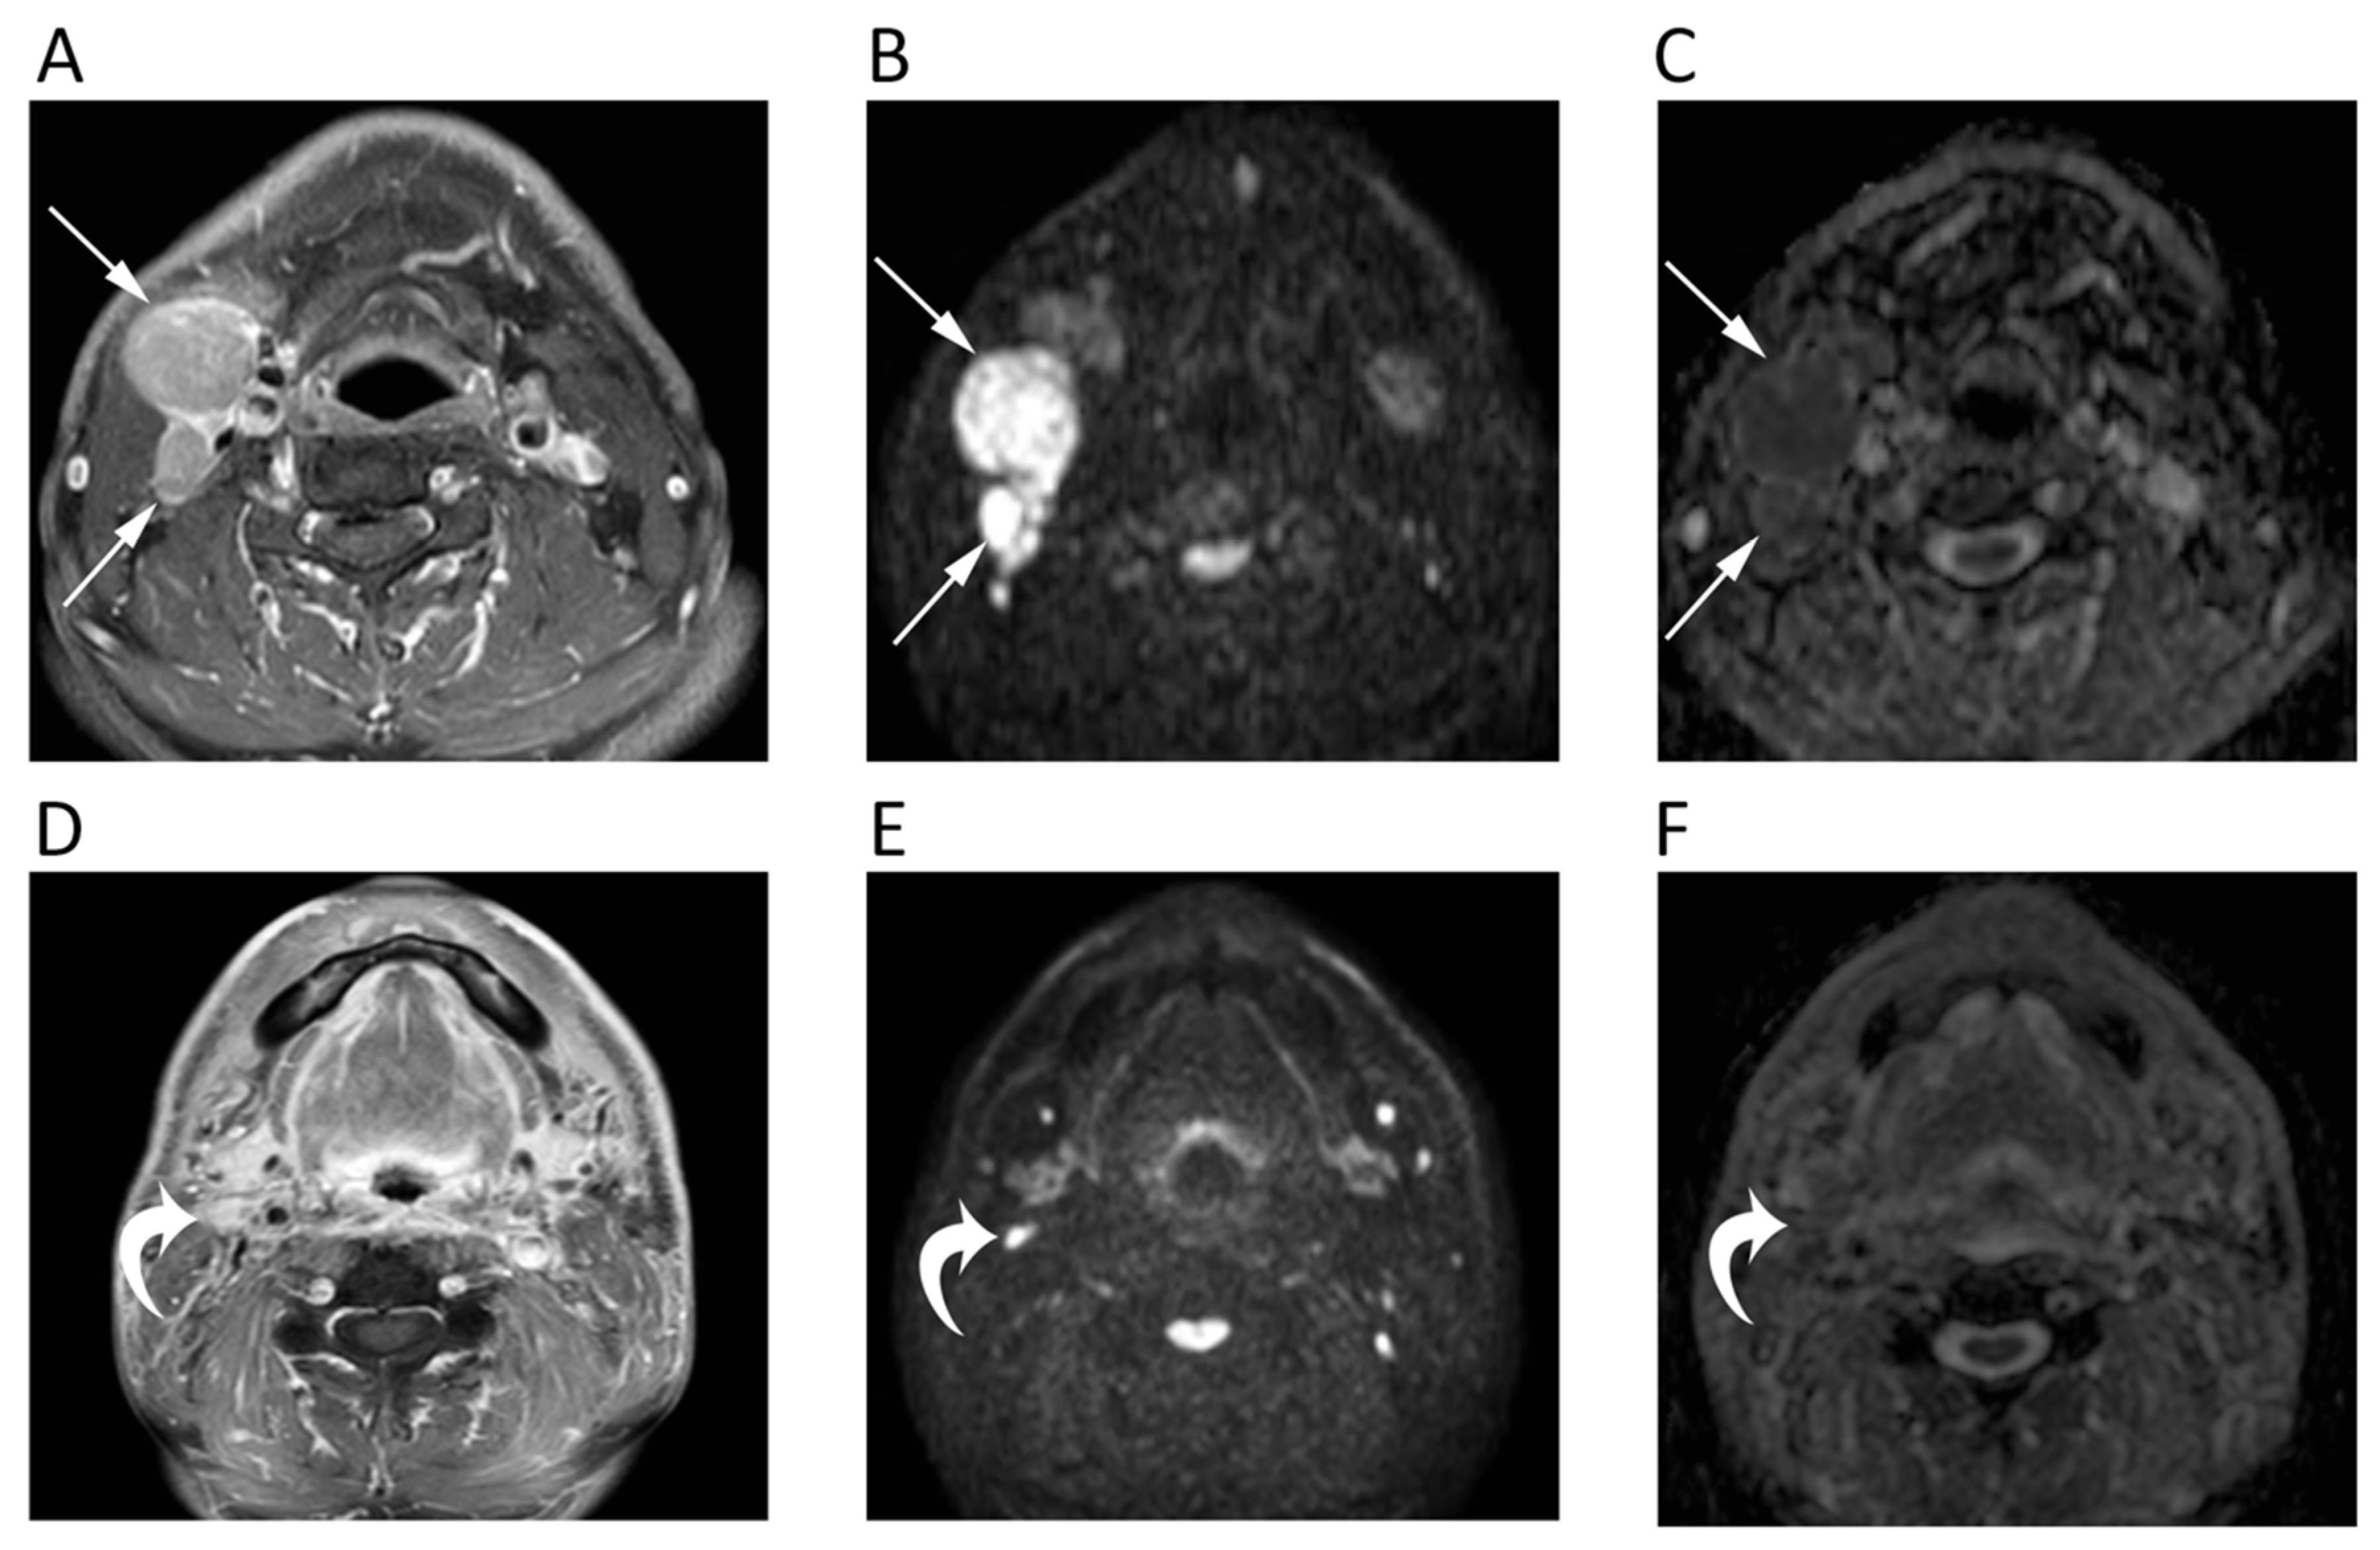

A diagnostic challenge is the differentiation of lymph nodal metastases from both benign nodes and lymphomatous locations, with controversial results reported in the literature. According to most studies, Abdel Razek et al. reported significantly (p < 0.04) lower ADC in malignant nodes (metastatic 1.09 ± 0.11 × 10−3 mm2/s, lymphomatous 0.97 ± 0.27 × 10−3 mm2/s) than in benign (1.64 ± 0.16 × 10−3 mm2/s) suggesting a mean ADC of 1.38 × 10−3 mm2/s as an optimal cut-off with accuracy, sensitivity, and specificity of 96%, 98%, and 88%, respectively (Figure 2) [11].

Figure 2.

MRI scans of a 65-year-old male patient with oropharyngeal squamous cell carcinoma and lymph nodal metastases. Contrast-enhanced T1w (A), high b-value DWI (B), and corresponding ADC map (C) before chemotherapy show round enlarged right cervical lymph nodes (arrows) with restricted pattern of diffusion (mean ADC: 0.891 × 10−3 mm2/s). The same images after treatment (D–F) show the good response to chemotherapy with normal size and unrestricted pattern of diffusion of the cervical lymph nodes (curved arrows).